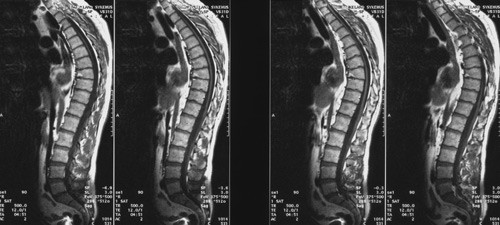

MR av columna viste mulig atrofi av torakal medulla (fig 1). MR av hjernen var normal. Ved isoelektrisk fokusering av spinalvæsken fant man to bånd, som ikke var til stede i serum. Vitamin B12-status var normal. Nevrografi var normal, men visuelt og sensorisk fremkalte responser viste sentral ledningsforsinkelse.

Bildeundersøkelser av sentralnervesystemet kan vise normale funn. I noen tilfeller finnes det atrofi av medulla spinalis, som var antydet hos vår pasient, og nær halvparten kan ha signalforandringer på MR av hjernen. MR-funnene i hjernen kan variere fra beskjedne høysignalforandringer i pyramidebanene til symmetrisk demyelinisering i parietooksipital området og kontrastoppladning i den aktive randsonen (1). Nevrofysiologiske undersøkelser kan vise en primært aksonal polynevropati, eventuelt med sekundær demyelinisering.